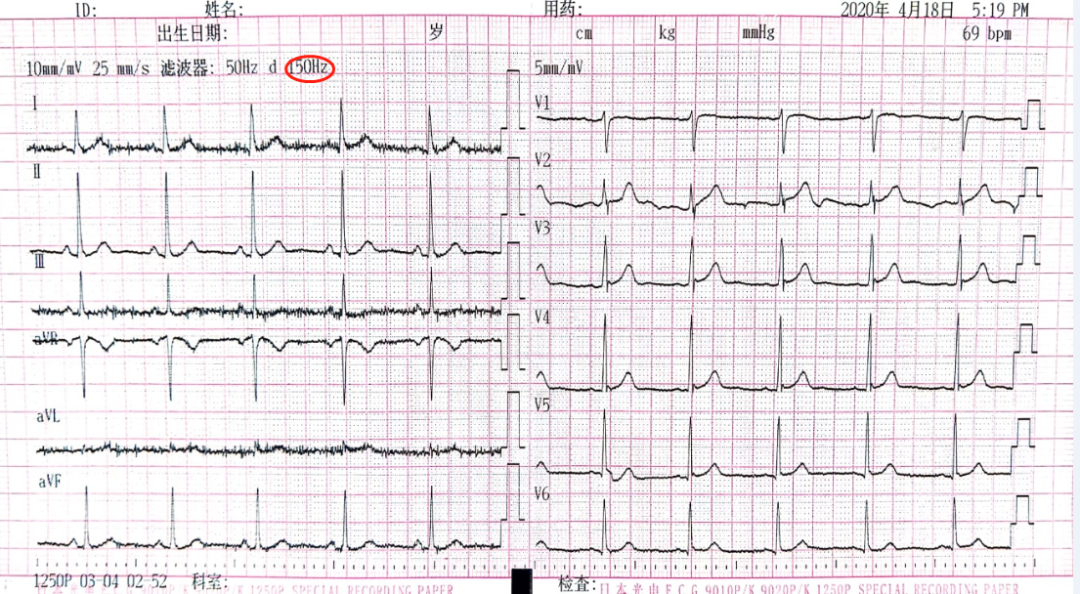

对于1250P机型来说,当肌电滤波打开时,可如图七所示。当肌电滤波关闭时,则高频滤波数值(75Hz、100Hz及150Hz三种状态)会在原肌电滤波显示处显示,如图八(150Hz)和图一小5(100Hz)。

图八 肌电滤波关闭,高频滤波(频响范围的上限)设定的数值显示在原肌电滤波显示处(150Hz)